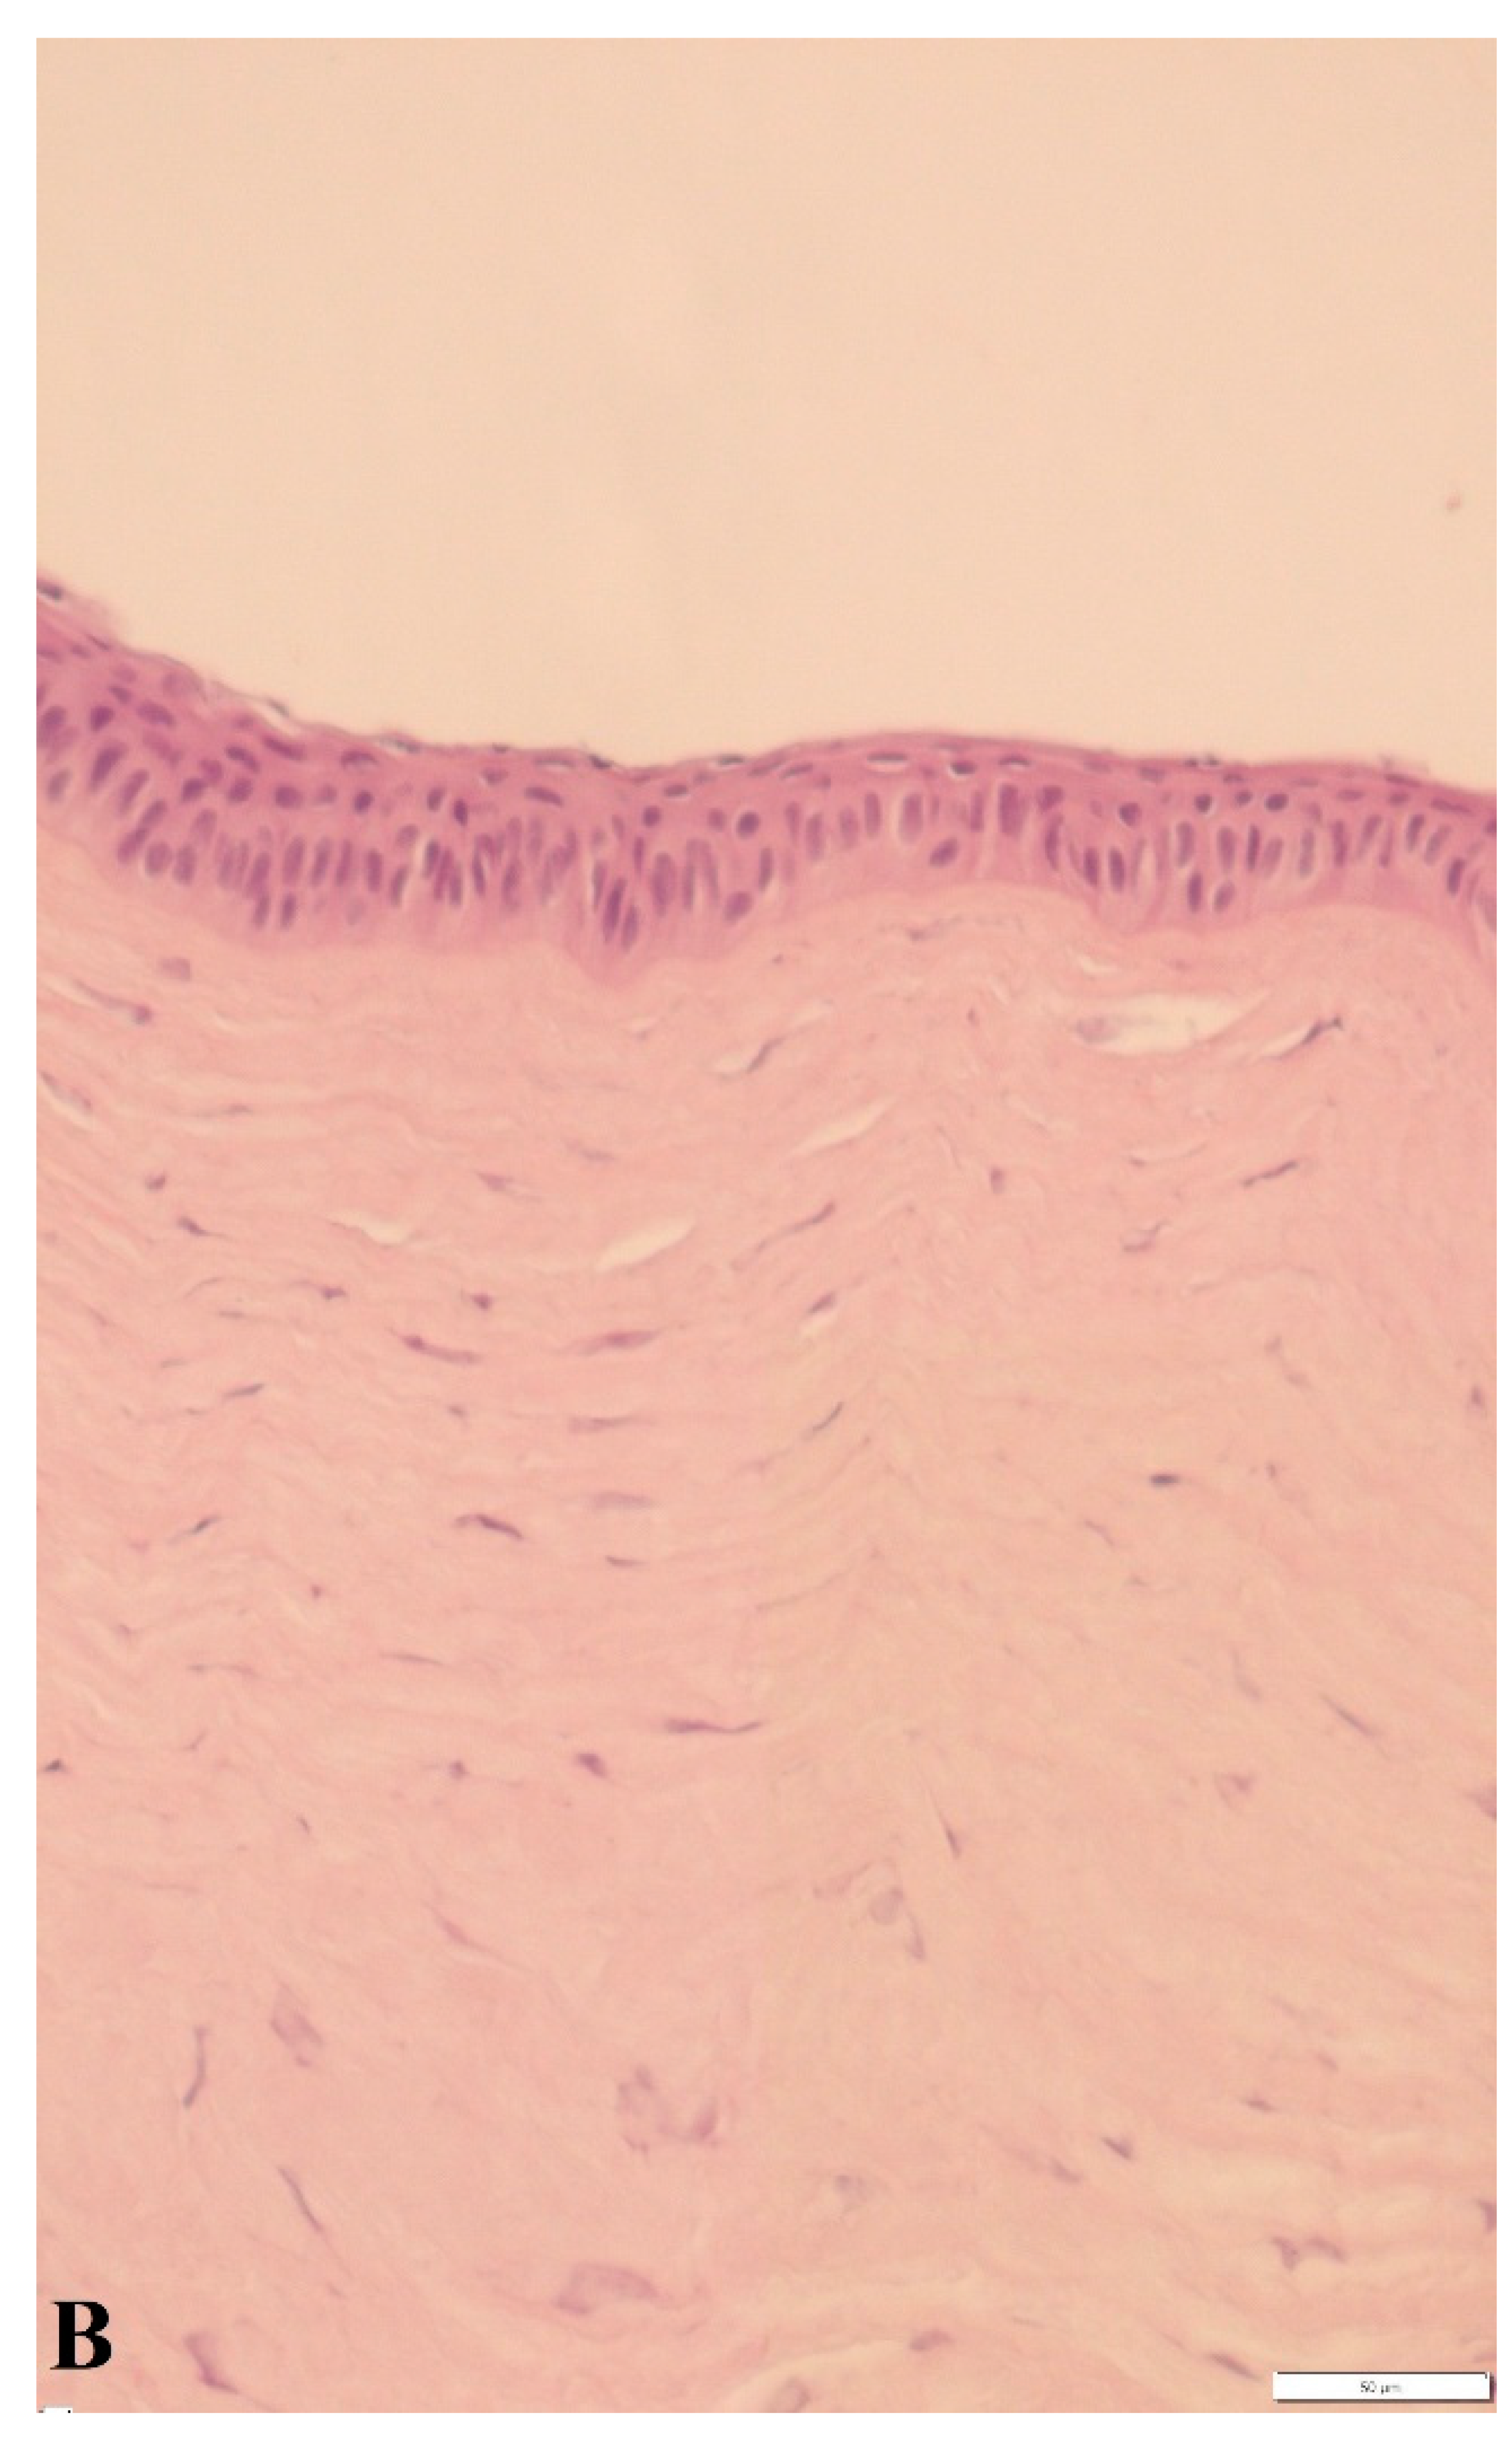

3.3. Histological Findings and Epidermal Thickness